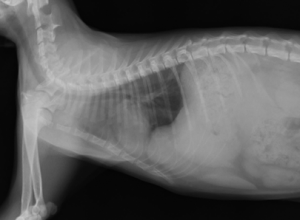

主訴:車にぶつかったとのことで来院されました。来院時、呼吸が早く、開口呼吸をしていました。レントゲン検査にて横隔膜ヘルニアが確認されました。

横隔膜ラインの不整と肝臓の変位が確認されました。